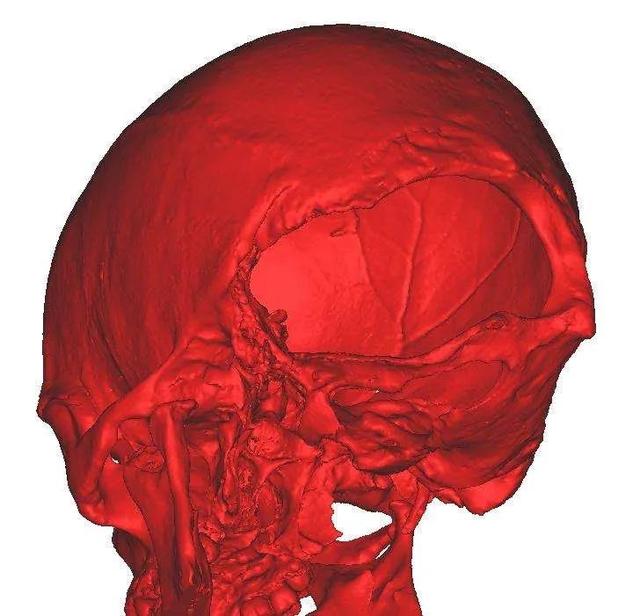

于是来到南昌市第三医院神经外科门诊,经过一系列的检查,头颅CT及MRI提示枕部存在一大一小颅骨缺损,其中大者达28*13cm,小脑萎缩明显,局部脑脊液充填,脑膜膨出伴少量脑膨出,要给如此巨大脑膜脑膨出行修补术,难度非常大,充分的术前检查、术前准备是必不可少的。

术前颅骨缺损和计算机模拟修复模型

术后第二天头颅CT复查未见脑积水形成,无异常出血。头颅CT三维重建提示颅骨缺损修补贴合良好。